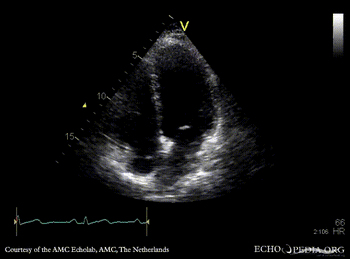

Contrast echocardiogram

AMC Echolab, AMC, The Netherlands

A4CH: jump rope IAS